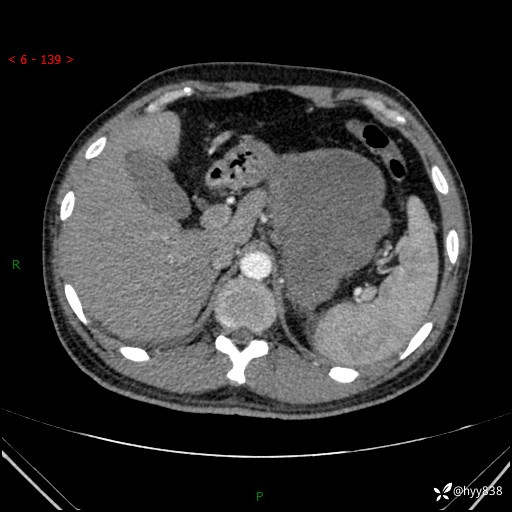

病例39岁/女,左侧腰痛入院。腹腔囊实性肿块,定位、定性---结果公布~

性别:男

年龄:39岁

简要病史:左侧腰痛待查,CT发现腹腔占位

腹部CT平扫+增强